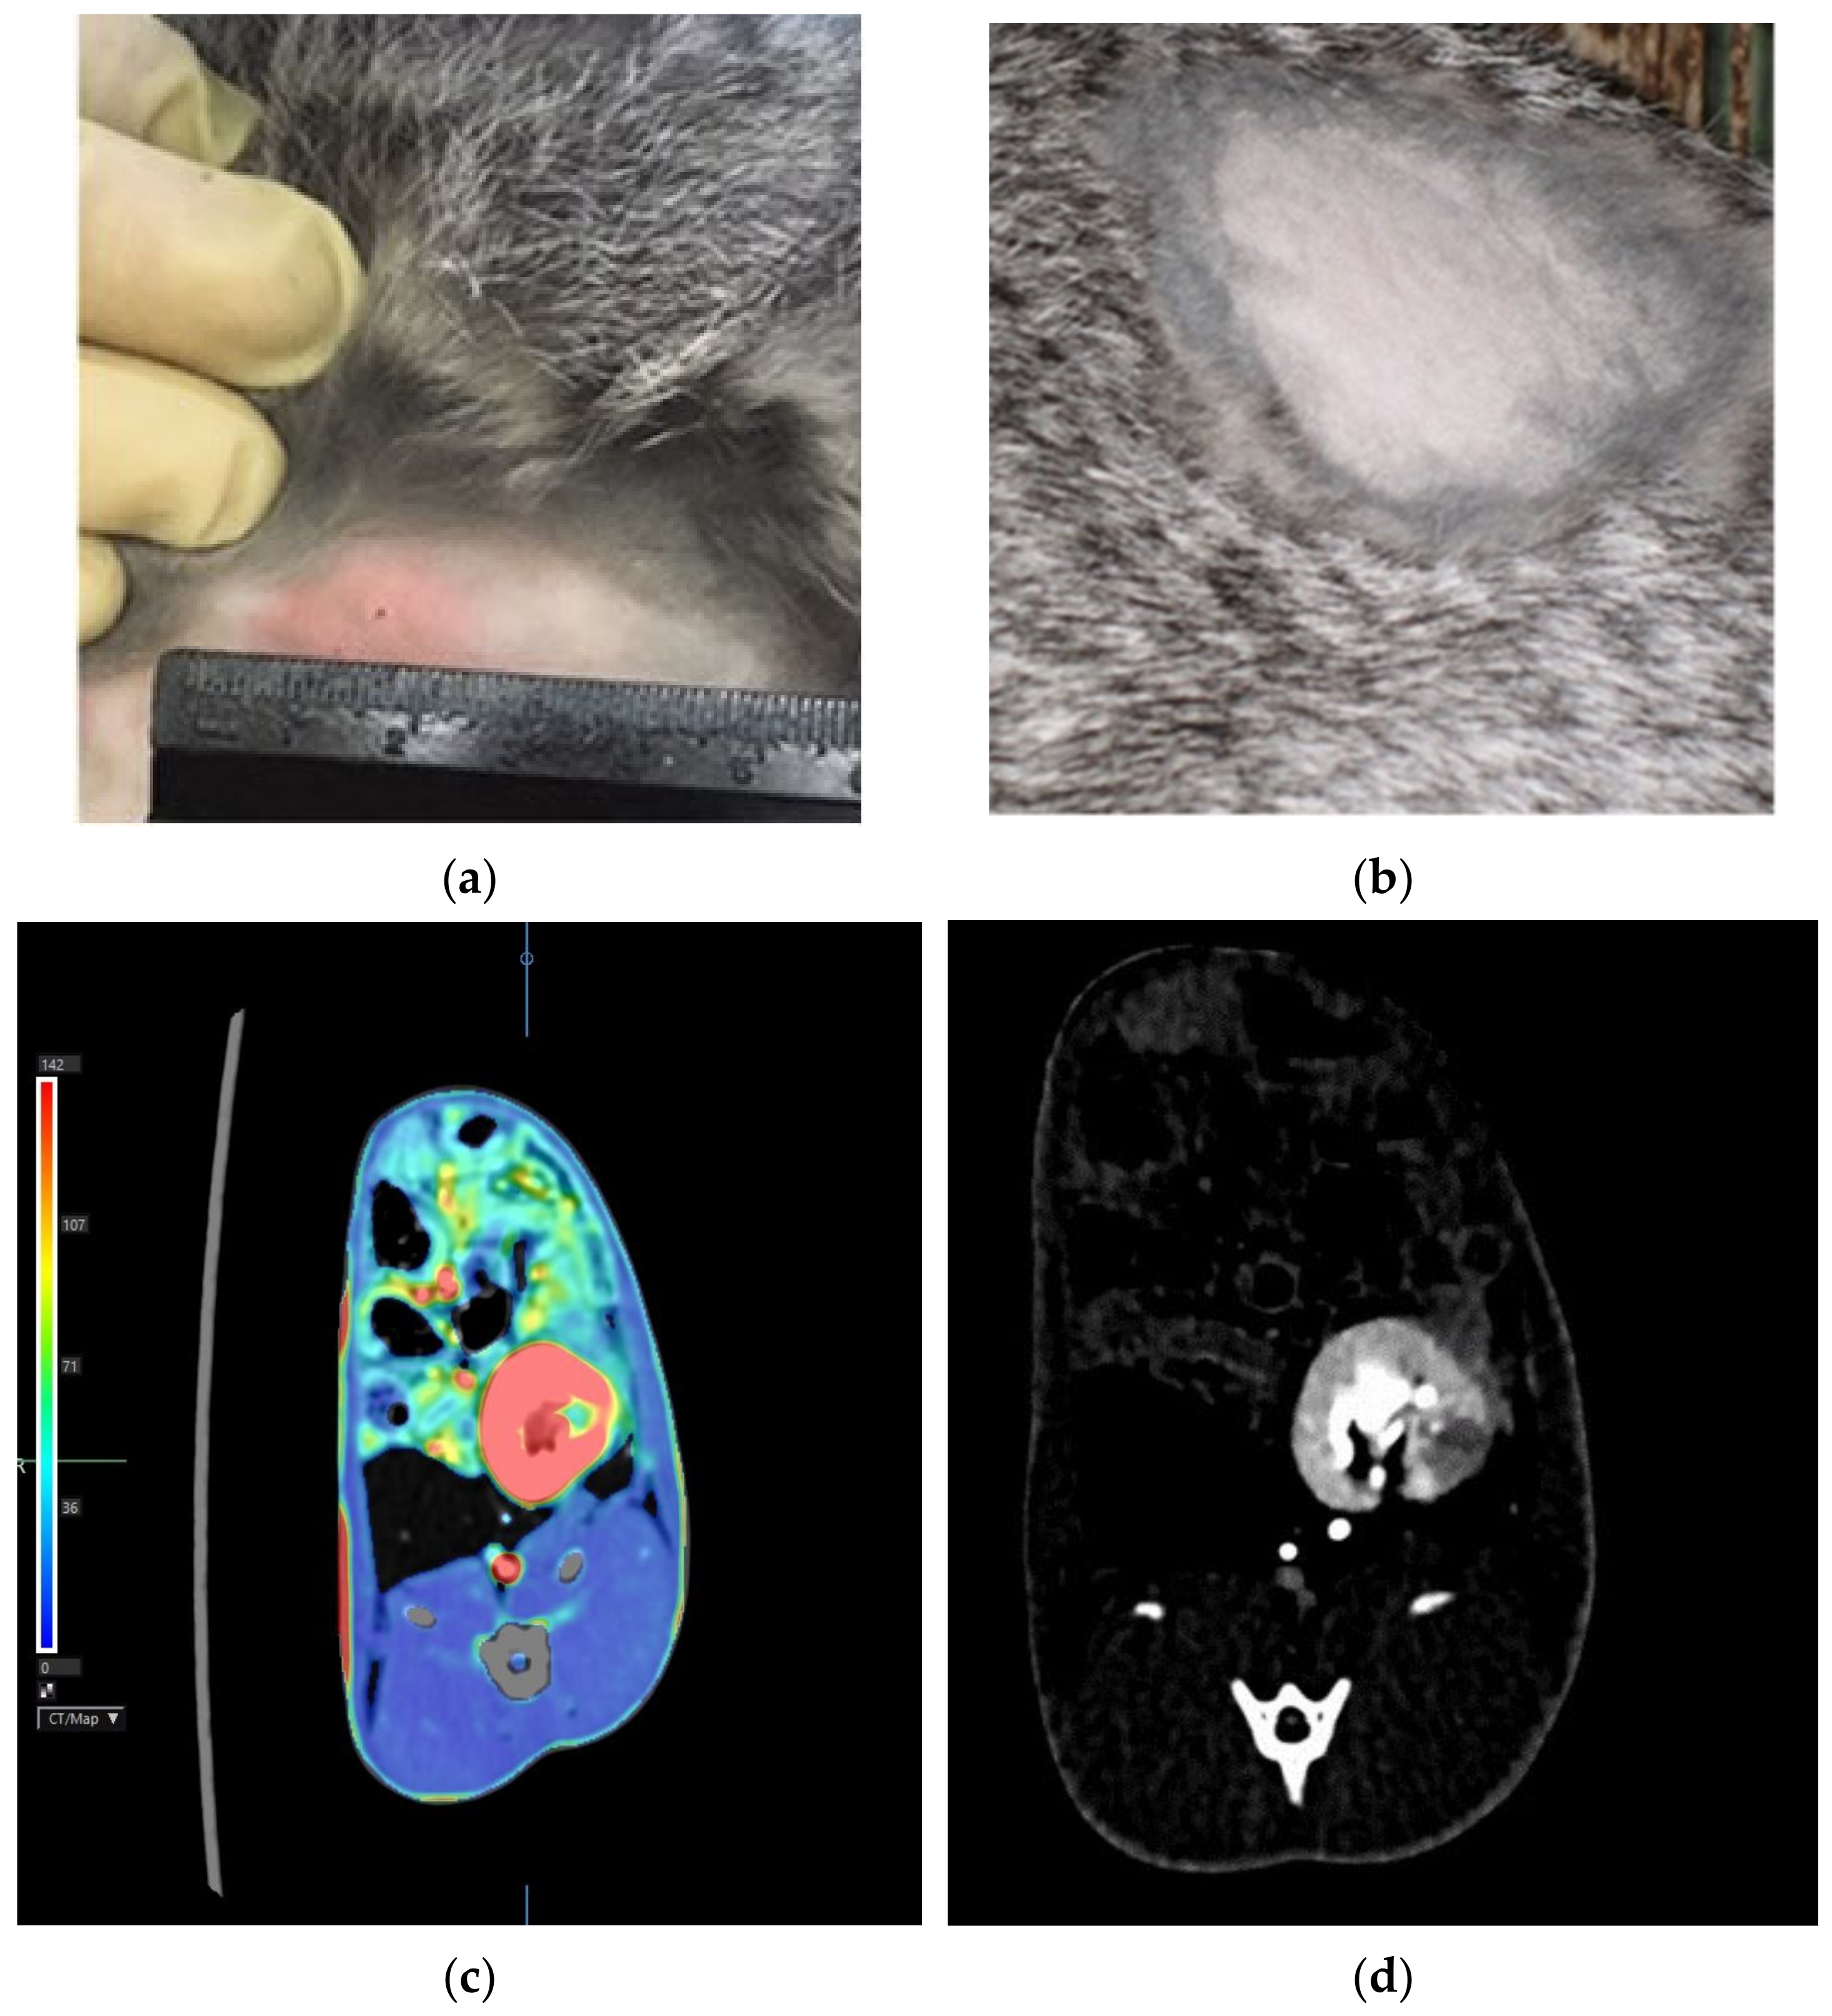

All challenged animals developed a specific inflammatory process in the kidneys with a characteristic immunological reorganization, which was confirmed by erythema of 15.3 ± 2.8 mm in size in response to Diaskintest® administration 18 days after the challenge and its absence (Figure 2a,b, respectively). According to the results of the abdominal computed tomography scan 30 days after the challenge, a clearly defined area of reduced perfusion was revealed in the left (infected) kidney (Figure 2c). During standard computed tomography, a destruction focus is visualized in this area (Figure 2d).

Figure 2.

Hyperergic erythema type reaction in response to intradermal administration of Diaskintest 30 days after the challenge (a)—infected rabbit; (b)—intact rabbit). Abdominal CT: (c)—a clearly defined area of reduced perfusion is determined in the left kidney (green color reflects the low blood flow compared to the remaining parenchyma (red)); (d)—the destruction focus (the hypovascular area) in the area during standard computed tomography.